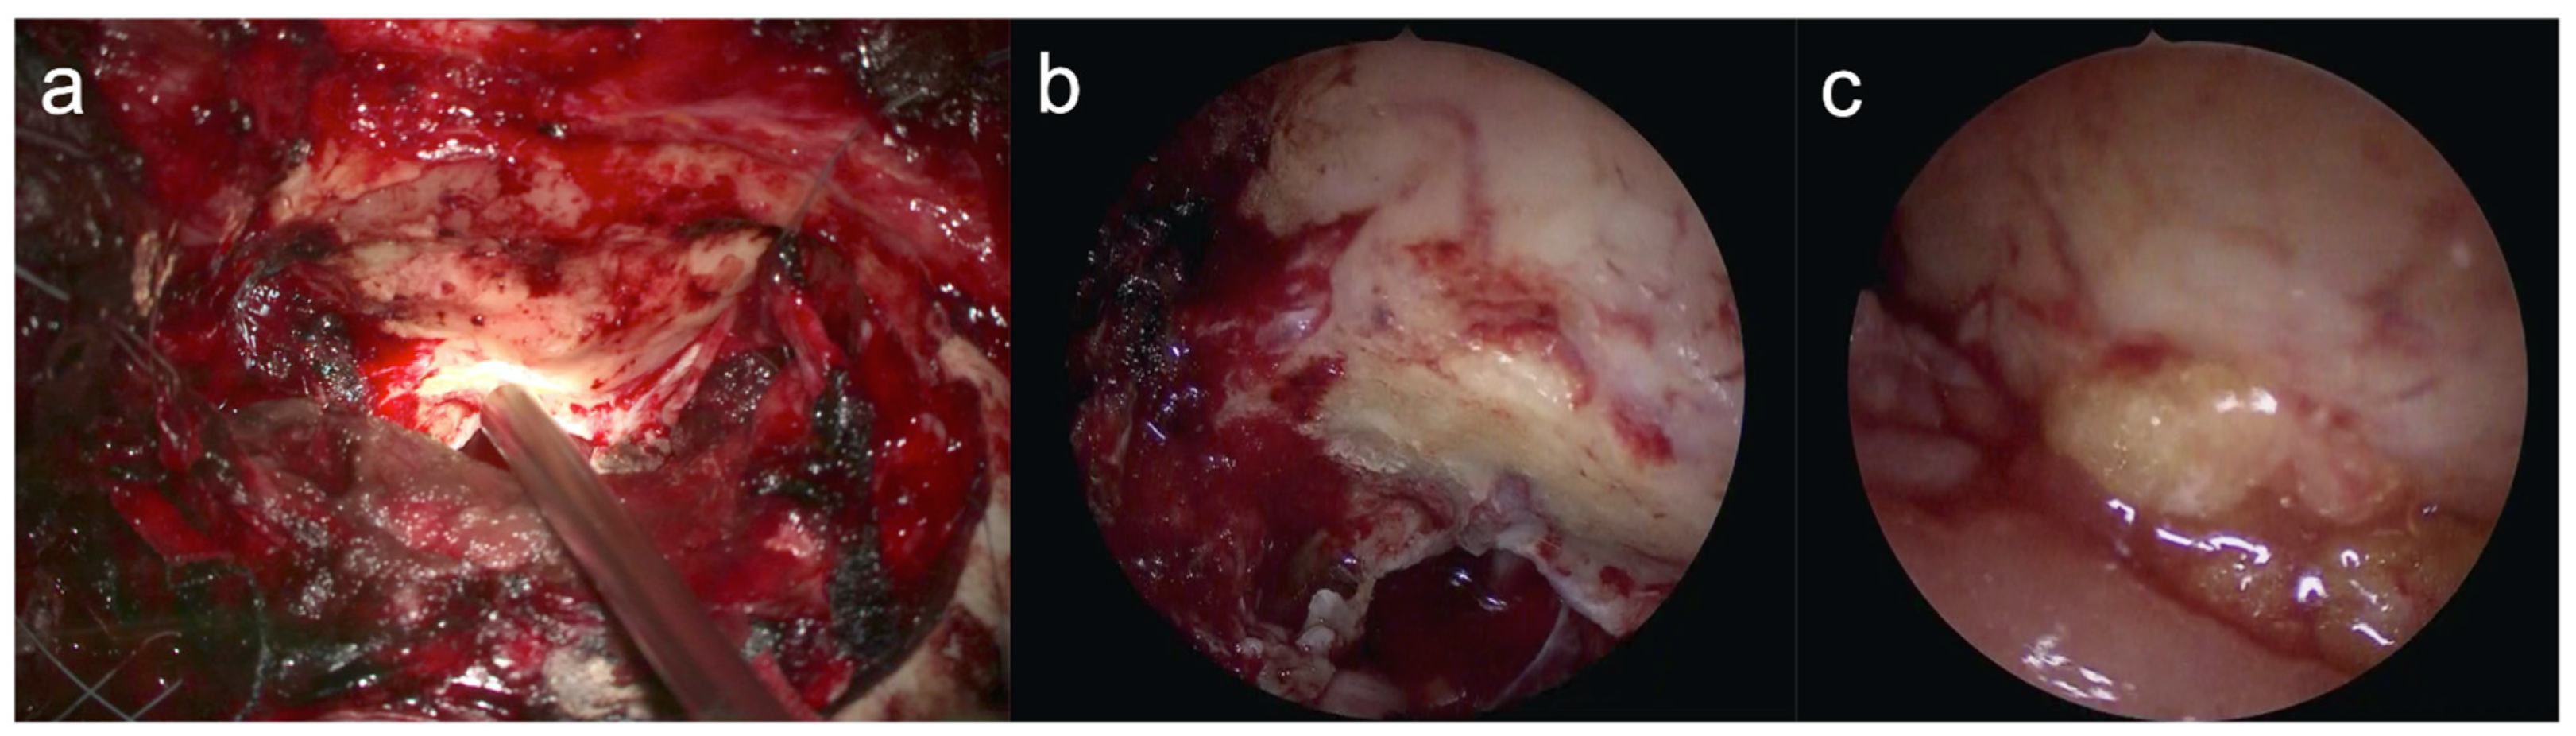

2.3. Intraoperative Precautions (Figure 3)